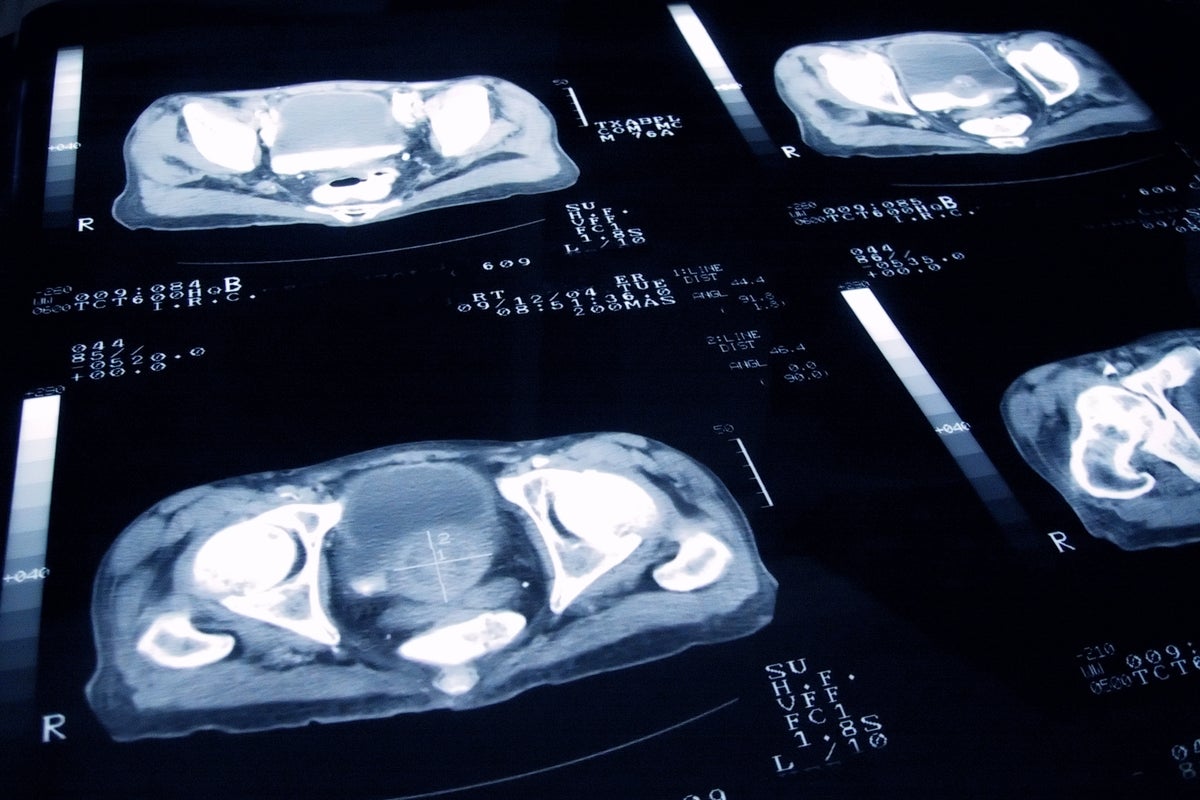

Former president received prostate cancer diagnosis last week after a routine exam uncovered a ‘small nodule’ Post navigationElon Musk endorses conspiracy theory around Biden’s cancer diagnosis 18-year-old woman dies after crashing her Range Rover in Cape Cod as she was leaving prom